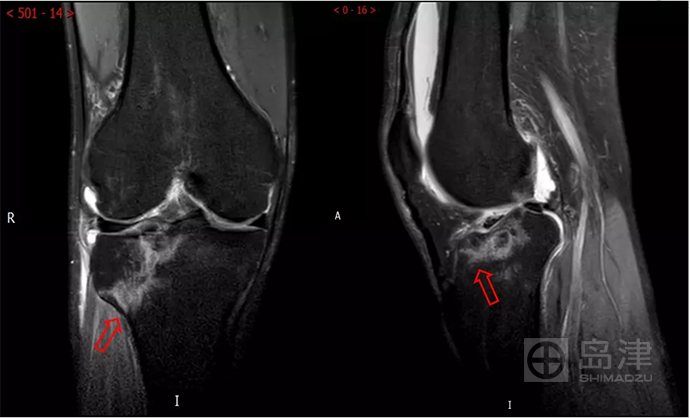

病例三:骨折征象显示

45岁男性,与孩子玩耍时,从一级台阶上蹦下即感右膝疼痛明显,无法行走。

右膝正侧位X线:未见骨折直接及间接征象 。

DTS 显示胫骨平台骨折 。

查 CT MR ,与DTS结果一致。

隐匿性骨折 DR无法发现

右胫骨平台隐匿性骨折

DTS可发现平片无法发现的骨折

CT结果与DTS一致

MRI结果与DTS一致

图像来源:西安市第九医院